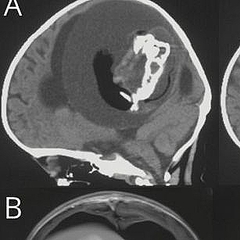

上記のように寄生性双生児は医学的には広く知られた事例ですが、「脳の中に胎児を吸収した事例」は非常に珍しいとのこと。今回報告された患者の脳のCTスキャン画像を見ると、脳の中に人間の骨格のようなものが写っていることが分かります。